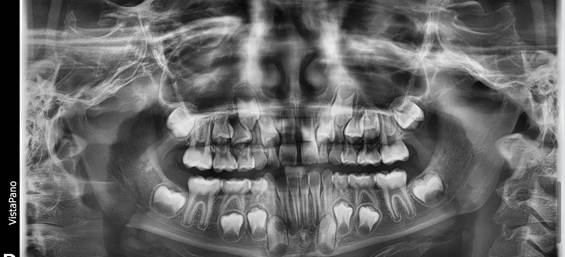

Radiografías

Las radiografías periapicales y la panorámica mostraron un desarrollo dental de un paciente de 7 años. (Fig. 10, 11 y 12)

Fig. 10 Radiografía Panorámica inicial

Fig.

11

Rx periapicales incisivos Fig. 12 Rx

periapicales molares y de mordida